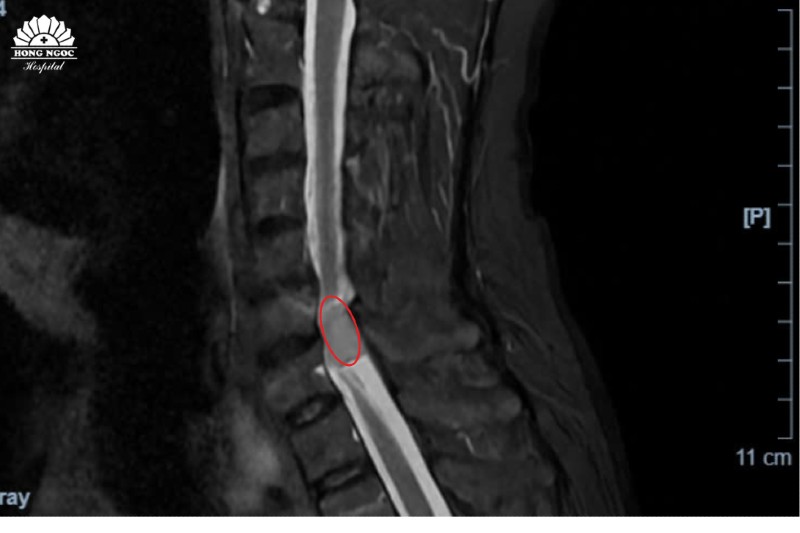

Vị trí khối u chèn ép tủy cổ qua phim chụp cộng hưởng từ (MRI)

Trực tiếp thăm khám cho bệnh nhân, PGS.TS.BS Hà Kim Trung (Chuyên gia hơn 30 năm phẫu thuật thần kinh, cột sống - BVĐK Hồng Ngọc) chia sẻ, u màng tủy cổ là bệnh lý hiếm gặp với các biểu hiện không rõ ràng, dễ nhầm lẫn với các triệu chứng của thoái hóa, thoát vị đĩa đệm cột sống. Kết quả chụp MRI cho thấy khối u đã chèn ép 1/2 ống tủy, khiến bệnh nhân có biểu hiện tê bì - yếu tứ chi.